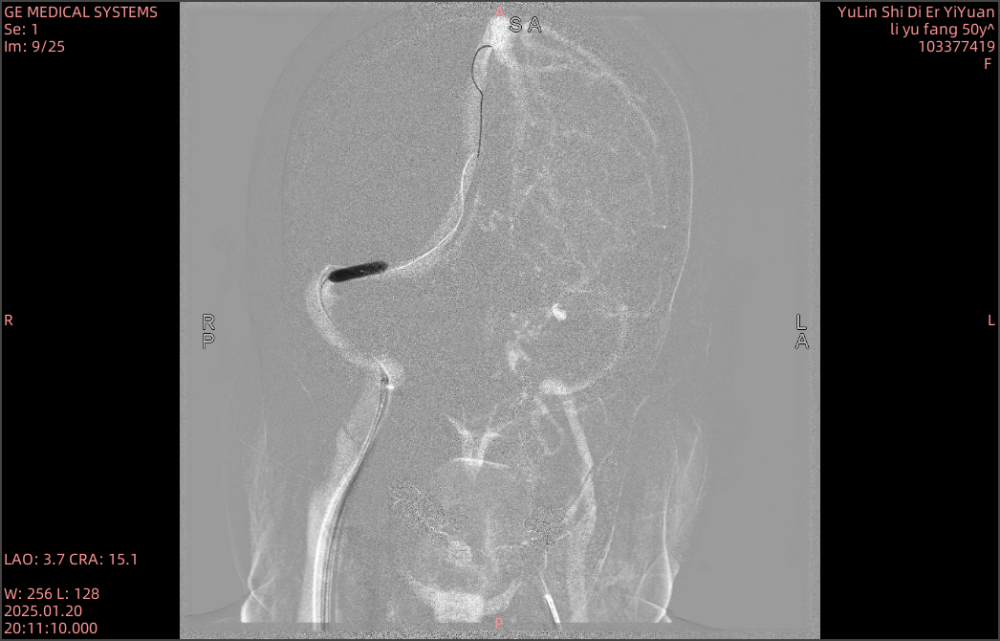

患者术中造影

术中球囊扩张

支架置入术后造影

术前MRV显示:左侧横窦闭塞,右侧横窦和乙状窦交界处存在狭窄。术中造影进一步明确为右侧横窦乙状窦交界处重度狭窄,狭窄程度>70%,同时左侧横窦闭塞,乙状窦纤细,与术前MRV结果相符。术中测压,经粗略计算,狭窄处近、远端压力差约为10mmHg。术中进行球囊扩张,支架置入术后造影显示,静脉窦狭窄处成形良好,可见清晰的金属支架影。